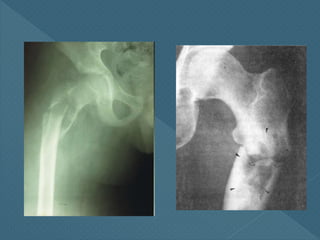

Patológica

Todo proceso que

provoca debilitamiento

del hueso

Carcinomas

metastásicos o

enfermedades del

esqueleto

Acorde Por traumatismo brusco enhueso libre de enfermedad Simplemente: fractura Stress Stress repetitivo sobre la zona Fracturas de fatiga o marcha Patológica Todo proceso que provoca debilitamiento del hueso Carcinomas metastásicos o enfermedades del esqueleto